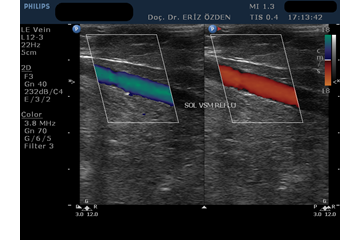

Bacak Venöz Doppler Nasıl Yapılır? Ultrasonografi cihazı Renkli Doppler özelliğine sahipse, damarların içindeki kan akımını renkli olarak görmek mümkündür. Renkli Doppler Ultrason adı verilen bu yöntem sayesinde damarlardaki daralmalar, pıhtılar ve tıkanıklar saptanır. Kan akım hızına yönelik ölçümler yapılır. Bacak atar ve toplar damarlarındaki problemlerde Renkli Doppler çok sık kullanılır. Toplardamarların içindeki kan akımı renkli olarak görülür. Kan akımının yönü, miktarı, damarlada geriye kaçış olup ulmadığı ve en önemlisi toplardamarlar içindeki pıhtılar tespit edilir. İnceleme önce hasta sırt üstü yatırılarak başlar. Kasıktan başlayarak ayak bileğine kadar tüm toplardamarlar incelenir. Bunun için hastanın bacağına jel sürülür ve ultrason cihazının başlığı cildinin üzerine dokundurulur. İnceleme hiç acı vermez. Renkli doppler yöntemiyle bacak içindeki toplardamarlar renkli olarak görülür. Kasıltan ayak bileğine kadar bacakta bulunan çok sayıda toplardamarın hepsi, ayrı ayrı, santim santim takip edilerek, içindeki kan akımı, pıhtı varlığı, damar yetmezliği açısından incelenir. Devamında hasta yüzüstü yatırılarak diz ve bacak arkasında yer alan toplardamarlar incelenir. Ardından hasta dik pozisyona getirilir. Bu aşamada, hasta dik duruken, yer çekimi ile damarlarda yetmezlik ortaya çıkıp çıkmadığına bakılır.

Bacak Venöz Renkli Doppler Tetkiki Neden Yapılır? Venöz Renkli Doppler tetkiki, bacak toplardamarlarındaki varislerin, yetmezliklerin ve pıhtı oluşumlarının araştırılmasında kullanılır. Uzun süre ayakta durarak çalışanlarda, ileri yaşlardaki kişilerde, çoğunlukla da bilinmeyen nedenlerle bacak toplardamarlarında yetmezlik olabilir. Normalde toplardamarlardaki kirli kan, devamlı olarak yukarı, yani kalbe doğru akar. Hastanın ıkınması, öksürmesi, uzun süre ayakta kalması gibi durumlarda kan geriye doğru akmamalıdır. Damar içindeki ince kapakçıklar geriye akımı önler. Kanın geriye doğru kaçış göstermesine reflü akım denir. Bu durum venöz yetmezlik olarak adlandırılır ve bacaklarda şişme ya da varislerin oluşmasına neden olabilir. Hangi damarlarda, hangi derecede yetmezlik olduğu Venöz Renkli Doppler Ultrasonografi tetkiki ile anlaşılır.